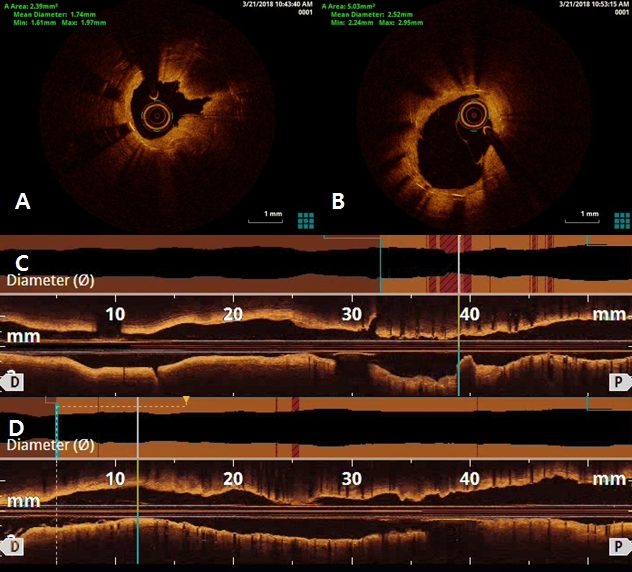

After 3 days later, we performed 2nd stage PCI for proximal LAD. CAG reveled moderate stenosis in proximal LAD (Figure 4A), so we examined optical coherence tomography (OCT) for further evaluation. It showed large amount of plaque (minimal lumen area [MLA] 2.62 mm2) (Figure 5A and 5C). We directly implanted 3.25 and 18 mm everolimus-eluting stent (Xience Alpine®), but follow-up CAG showed mild under-expansion, so we did additional ballooning using 3.25 x 10mm non-complaint balloon (Figure 4B and 4C). Follow-up OCT and CAG showed good distal flow without significant residual stenosis. (post-PCI cross sectional area [CSA] 6.65 mm2) (Figure 4D, 5B and 5D). Because of no-reflow phenomenon for RCA in previous PCI, we performed follow-up CAG and OCT for RCA. CAG and OCT showed stent underexpansion with neointima rupture and large amount of residual thrombi in mid RCA (MLA 2.39 mm2) (Figure 6A, 6B, 7A and 7C). So we did ballooning using 3.25 x 10 mm non-complaint balloon for mid RCA (Figure 6C). Follow-up CAG and OCT showed good distal flow without significant residual stenosis. (CSA 5.03 mm2) (Figure 6D, 7B and 7D). He was discharged without any complications.

Figure 5. Optical coherence tomography (OCT) findings of left anterior descending artery (LAD). OCT showed large amount of plaque in proximal LAD (A and C). There was no significant residual stenosis in proximal LAD after stenting and additional ballooning using non-complaint balloon (B and D)